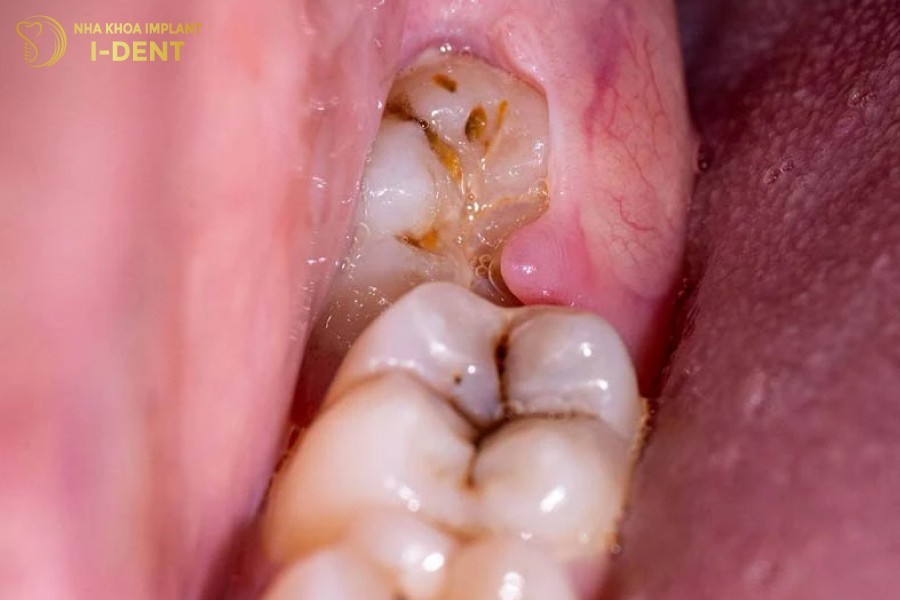

- Răng số 8 gặp các vấn đề như bị sâu, bị viêm nhiễm, nha chu, chảy máu nướu,.. tạo điều kiện thuận lợi cho vi khuẩn xâm nhập, gây viêm nhiễm lan rộng sang các răng kế cận và ảnh hưởng đến các tổ chức quanh răng như tủy răng, xương hàm, dây thần kinh.

- Hình dạng và kích thước răng số 8 bất thường, quá to, quá nhỏ hoặc bị dị dạng, khó vệ sinh và dễ gây nhồi nhét thức ăn với răng bên cạnh, lâu ngày gây sâu răng, viêm nha chu,…

Răng số 8 bị sâu gây đau nhức khó chịu.